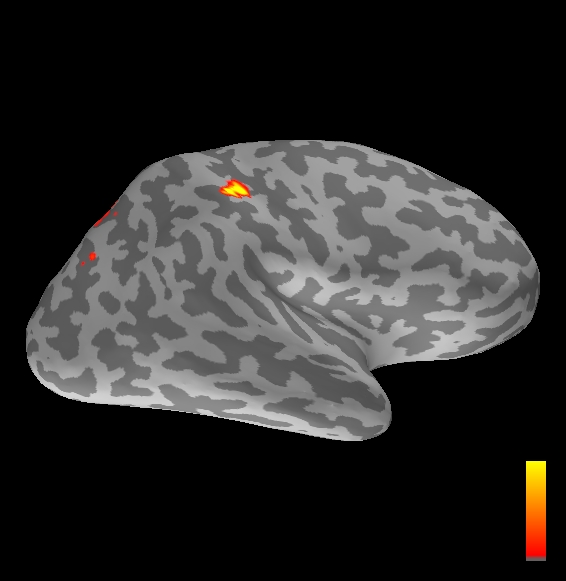

5.2 Results

We applied the ASMC sampler to MEG topographies taken from the above recordings by selecting specific time points according to the previous analysis; the parameter values in the algorithm were the same as those used for the analysis of synthetic data, with the only exception of the noise standard deviation , here estimated from the pre–stimulus interval. In order to validate the results of the ASMC, we also computed source estimates using three other methods: a PF, that approximates the posterior distribution for the current dipoles conditioned on the data up to the selected time point; dSPM, which is based on a distributed source model with an –prior, and consists in normalizing the Tikhonov regularized solution by the noise standard deviation; and sLORETA, which is similar to dSPM but is claimed to have a smaller localization bias. Figure 4 shows the results at , and ms after the stimulus onset. The results are visualized on a computer representation of the brain obtained by “inflating” the cortical surface: gray levels contain the anatomical information, light gray representing gyri and dark gray representing sulci; the activity estimate is coded in color scale, increasing from red to yellow. Importantly, this visualization allows activity in the sulci to be clearly visible; on the other hand, since neighbouring volumes may be moved apart by the inflation process, distinct activity regions are often due to underlying volumetric masses that are very close to each other.

Before describing the results, let us comment on the qualitative difference between the images produced by the ASMC sampler and the PF, on the one hand, and those produced by dSPM and sLORETA, on the other. First of all, we point out that all the quantities shown in the images of Fig. 4 are somehow related to the probability of activation at specific locations. Indeed, for both the ASMC and the PF we plot the approximation of the intensity measure (3.8); for any single grid point, this value can be interpreted as the probability of a dipole being at that location, while it integrates, over a given volume , to the mean number of dipoles within . As for dSPM, the represented quantity is a statistical value that is –distributed under the null–hypothesis of zero activity; as a direct consequence, it also yields a probability of activation, which is however not constrained to be dipolar. Similar considerations apply to sLORETA, although with a different statistical distribution. Importantly, the representation of the results is clearly affected by the setting of the visualization threshold. Owing to the explained differences between the methods, it seems reasonable to use a different value for each method. At the same time, since the plotted quantity is a probability of activation, it seems right to use the same thresholding for different time points. In this connection, the thresholds in Fig. 4 have been chosen by hand following the guidelines just outlined.

Using the same thresholding and parameters at different time points makes the four methods respond differently to the diverse intensities of the different sources. Whenever a stronger source is active, both sLORETA and dSPM will tend to produce widespread estimates, while weaker sources will be represented as small active areas. The behaviour of the ASMC and of the PF is the opposite: a stronger signal will lead to a precise localization of a dipolar source, and then to a focal marginal distribution for the location; a weaker signal will translate to higher uncertainty on the source position, and therefore a more widespread posterior map.

The phenomenon just described is indeed clearly visible in Figure 4. At ms, all the methods correctly identify the rather strong activation in the contra–lateral primary somatosensory cortex: the ASMC and the PF provide very focal maps, while dSPM and sLORETA provide compatible widespread estimates; dSPM also exhibits a more posterior peak which does not fit with the commonly agreed models of the response to median nerve stimulation; this may be due to the formerly described brain inflation.